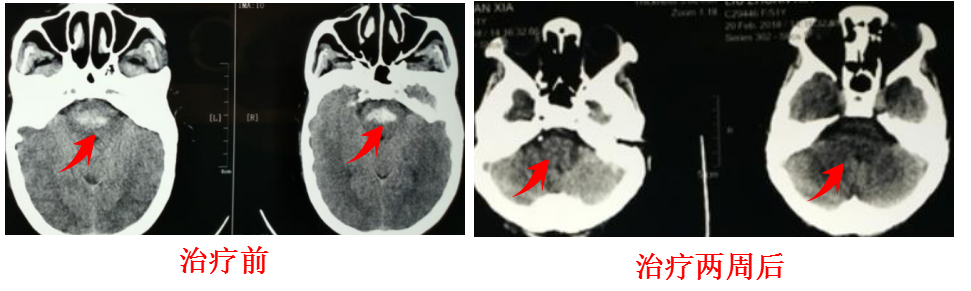

患者女性,54岁,距离过年只有一周了,突然瘫痪、失语、神志不清,经检查提示脑干出血,转入我科。

入院后患者神志昏迷,呼吸微弱,立即给予气管插管,并第二天气管切开呼吸机辅助呼吸,使用营养神经、脱水减轻水肿、抑酸护胃、清除氧自由基、控制血压血糖平稳并积极预防并发症等对症处理,两周后复查头部CT见脑干出血完全吸收,此时患者已经清醒,完全脱离了呼吸机,一月后出院康复。

两月后生活完全自理。